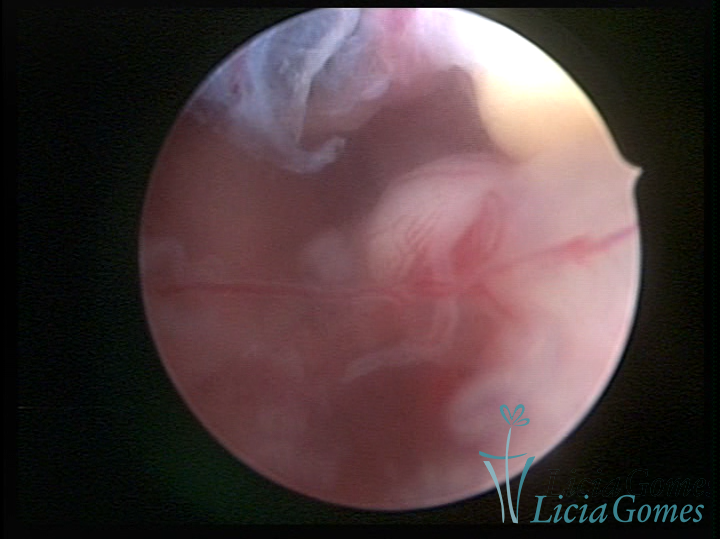

A histeroscopia permite analisar as características da superfície endometrial, não podendo avaliar a profundidade ou o grau de invasão miometrial.

Mas poderá verificar se as lesões são do tipo: focal; regional ou difusa

Este pode apresentar uma gama variável de aspectos macroscópicos, com aspecto pseudopolipoide; lembrando tecido cerebroide ou com reação deciduoide;a vascularização superficial é mais evidente e com vasos em formatos de saca-rolha ou espirais visualizando também a vascularização com atípias, com aumento do calibre dos vasos superficiais, pode ser encontrado também tecido em necrose, poderá haver um pequenos dendritos (papilomatoso).